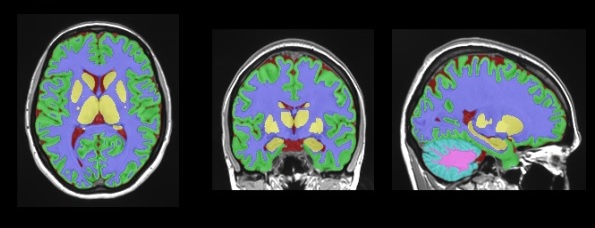

vol2Brain is capable of analyzing up to 135 regions of the brain from magnetic resonance images (MRI), offering information on the volumes of the tissues of the intracranial cavity (ICC) as well as some macroscopic areas such as the cerebral hemispheres, the cerebellum and the brain stem.

Likewise, vol2Brain also provides the volumes and asymmetry indices of cortical and subcortical structures, of great importance in the neurological field, and measurements of cortical thickness. “All this information”, highlights José Vicente Manjón, researcher of the IBIME-ITACA group of the UPV and one of the coordinators of vol2Brain, “is key to advance in the knowledge of neurological diseases”.